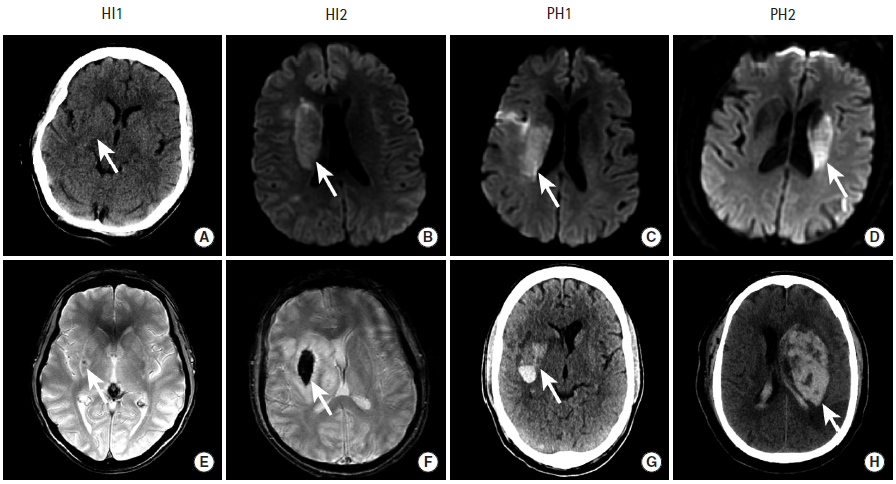

缺血性脑卒中后的出血性转化

图10

本组图片给出了4例患者的影像学检查,患者在接受血管内治疗完成血运重建后,出现了缺血性脑卒中后的出血性转化,这些患者的出血性转化分别属于4种类型:HI-1型、HI-2型、PH-1型、PH-2型。

出血性脑梗死(Hemorrhagic Infarction,HI)

HI-1型:沿梗死边缘的小的点状出血

HI-2型:梗死区内片状出血,无占位效应

脑实质出血(Parenchymal Hematoma,PH)

PH-1型:有血肿形成,占位效应轻,小于梗死面积的30%

PH-2型:血肿超过梗死面积的30%,有明显占位效应以及远离梗死区的出血